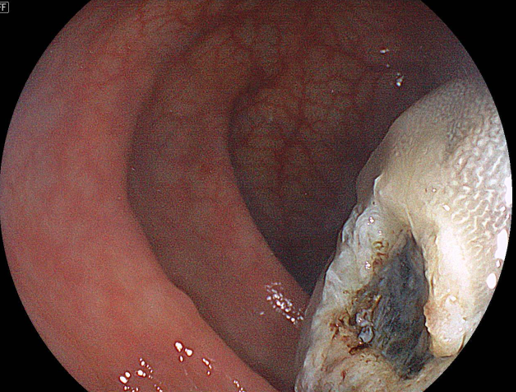

ここで、治療に対して大きな支障となるのが、大型腫瘍

を栄養するための動静脈がこの茎部(けいぶ:くきのこと)

には存在しているため、術中出血・後出血(こうしゅっけつ)

のリスクは、平坦な病変よりも、高いです。

実際の手技:粘膜下層(ねんまくかそう)に局注液を

注入後、十分なマージン(切除断端を陰性にするための距離)

を確保してからスネアリング後に、この症例は凝固波で血管

を処理してから、切除(せつじょ)しました。

切除後の潰瘍底(かいようてい):術直後の出血なく切除

されました。

切除後の潰瘍底に後出血予防のクリップを追加しました。